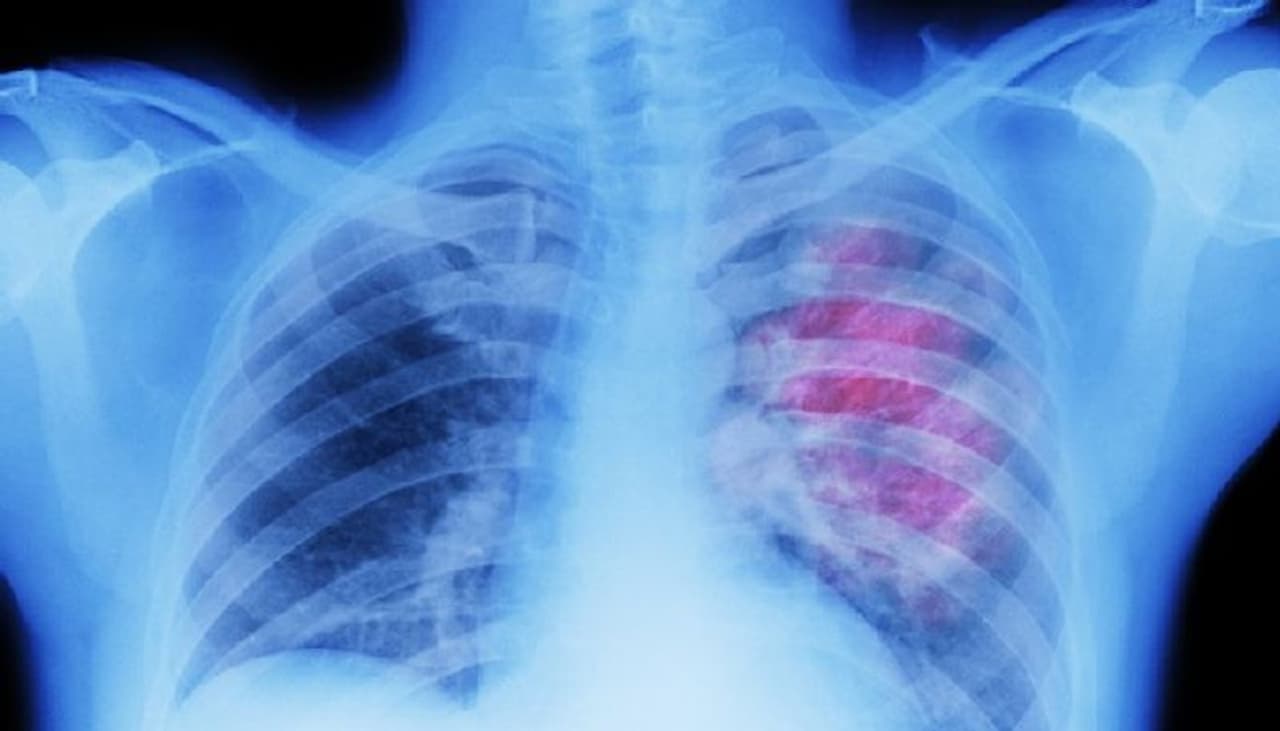

അടിസ്ഥാനപരമായി കൊവിഡ് ശ്വാസകോശ രോഗമായാണ് കണക്കാക്കപ്പെടുന്നത്. അതുകൊണ്ട് തന്നെ ഏറ്റവുമധികം ബാധിക്കാനിടയുള്ള അവയവവും ശ്വാസകോശം തന്നെയാണ്.

കൊവിഡിന് ശേഷവും ശ്വാസകോശം ഇത്തരത്തില് പല പ്രശ്നങ്ങള് നേരിട്ടേക്കാം. ശ്വാസതടസം, നെഞ്ചില് വേദന, അസ്വസ്ഥത, ശ്വാസമെടുക്കുമ്പോള് അസാധാരണമായി ശബ്ദം പുറത്തുവരിക, ഇക്കാരണങ്ങള് കൊണ്ട് ഉറക്കം നഷ്ടമാവുക എന്നീ പ്രശ്നങ്ങളും 'ലോംഗ് കൊവിഡി'ല് ഉണ്ടാകാം. ഇവയും ഗുരുതരമായ രീതിയില് തുടരുകയാണെങ്കില് ഡോക്ടറെ കണ്ട് വേണ്ട പരിഹാരം തേടണം.